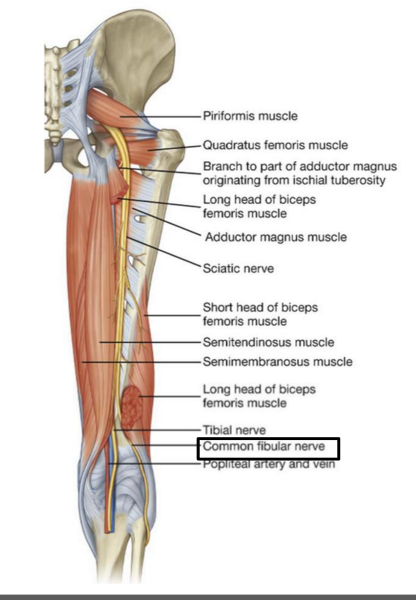

The sciatic nerve is formed from ventral rami from spinal cord levels ________-

L4 - S3

What is the path of the sciatic nerve?

exits the pelvis through the greater sciatic foramen. IN the posterior gluteal region, located inferior to piriformis m

Into which two nerves does the sciatic nerve bifurcate?

tibial and common fibular

The common fibular nerve is formed from ventral rami from spinal cord levels _______

L4 - S2

The common fibular nerve is the (lateral/medial) division of the sciatic nerve

lateral

What muscle does the common fibular division of sciatic nerve innervate?

ONLY biceps femoris short head

origin course and distribution of sciatic nerve

O L4-S3

C leaves pelvis through greater sciatic foramen inferior to piriformis; enters gluteal region; descends deep to biceps femoris; bifurcates into tibial and common fibular nerves at apex of popliteal fossa

D no muscles

O C D of common fibular nerve

O sciatic nerve